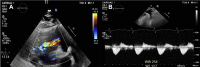

A 40-Year-Old Man With Tricuspid Atresia, Status Post-Fontan, With Severe COVID-19 Pneumonia and Pneumothorax

We report a case of COVID-19 in an adult single-ventricle patient post-Fontan-to our knowledge, the first report in this population documenting the use of the latest management recommendations for this novel disease. Additionally, this patient had significant pre-existing ventricular dysfunction, valvular disease, and comorbidities including HIV. (Level of Difficulty: Advanced.).